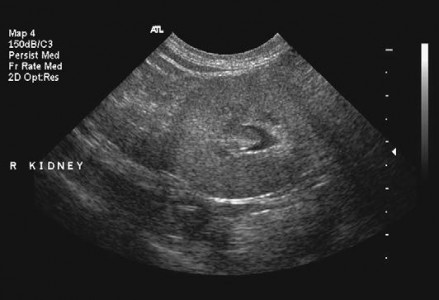

La mayoría de las ocasiones en las cuales recibimos ecografías indicando ectasia renal, emitimos el diagnóstico final de ectasia piélica simple, la cual supone una dilatación leve o moderada de la pélvis renal, que no está asociada a otras anomalías morfológicas de las vías urinarias. Se desconoce la etiología (lo que la ocasiona) y menos aún el pronóstico de la misma.

Si la dilatación de la pélvis es mayor a 20 milímetros, se le cataloga como hidronefrosis, y supone otro tipo de manejo.

Si es una dilatación menor a 10 milímetros, se recomienda vigilancia; en cambio si la dilatación es entre 10 y 20 milímetros, amerita tratamiento antibiótico profiláctico seguido de la evaluación por el urólogo.